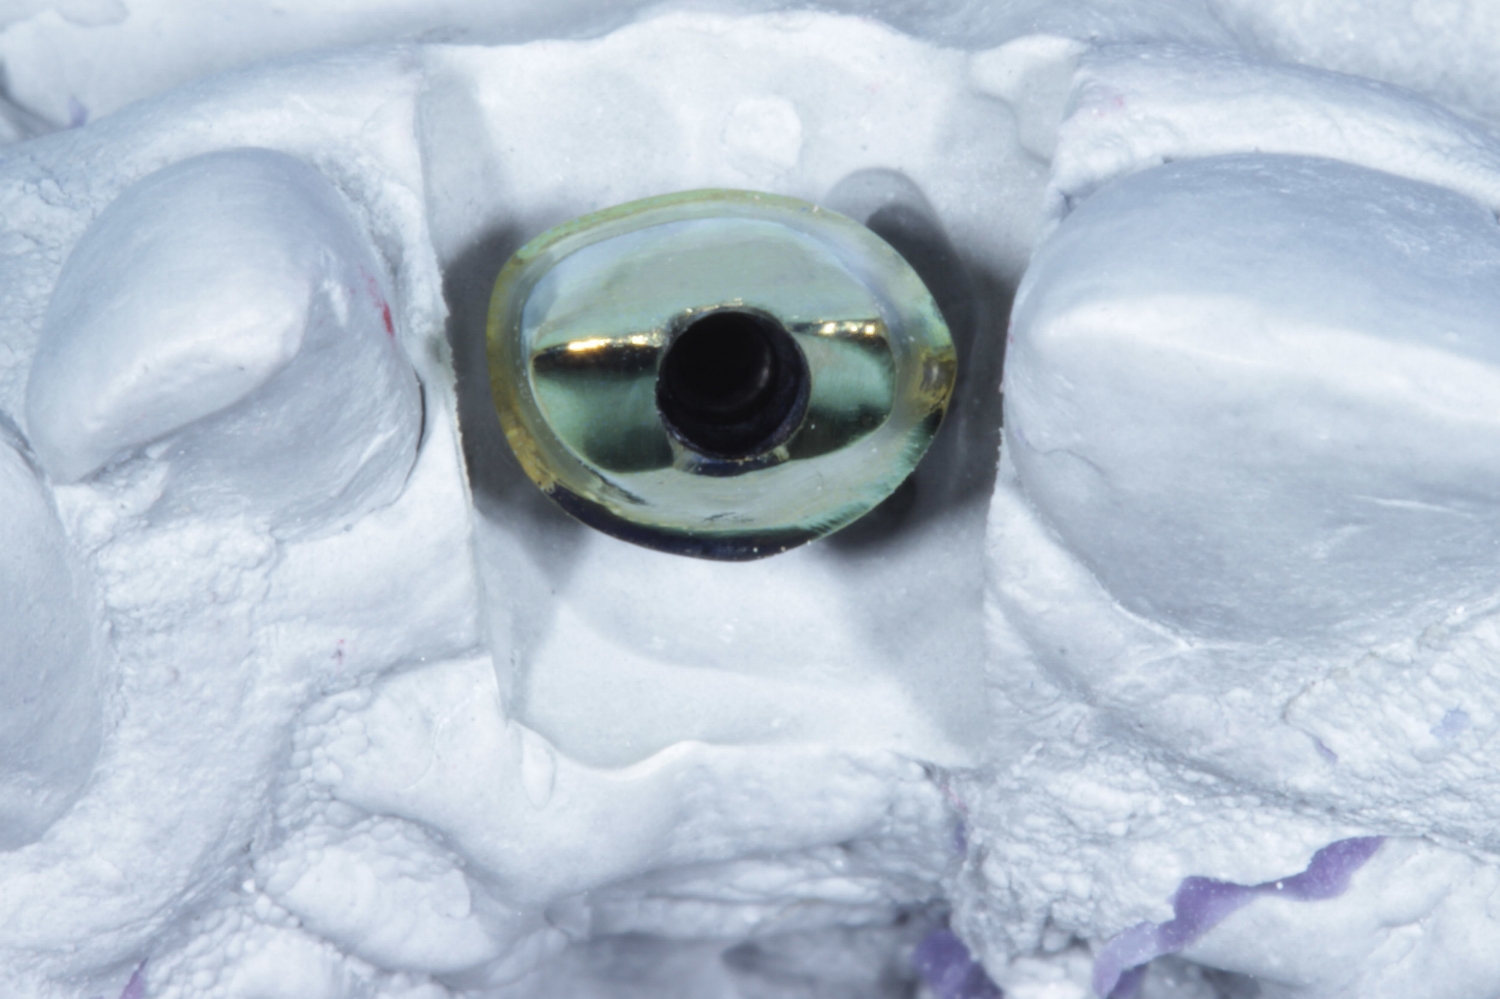

Gold hue for improved gingival aesthetics.

Fully customised abutments, providing improved strength over TI Bases.

The complete implant restoration package, this includes a custom gold anodised titanium abutment, clinical screw and an all ceramic crown for a fixed price of only £293!

As our customer you will receive; the finest “custom”, hybrid, two-piece implant abutment system. This gives you the amazing strength and reliability of a Titanium connection while still benefiting from the beauty of Zirconia.

The main complaint of the stock 'Ti Base' is that they have a sudden and uncontrolled emergence profile in relation to the crest of the bone, this often causes far too much pressure on the soft tissue and in some cases the bone, resulting in blanching and subsequently resorption. There are also concerns over their short height for strength and bond surface.

Customised margins depth- easy cement removal to avoid Peri-implantitis

Perfectly shaped emergence